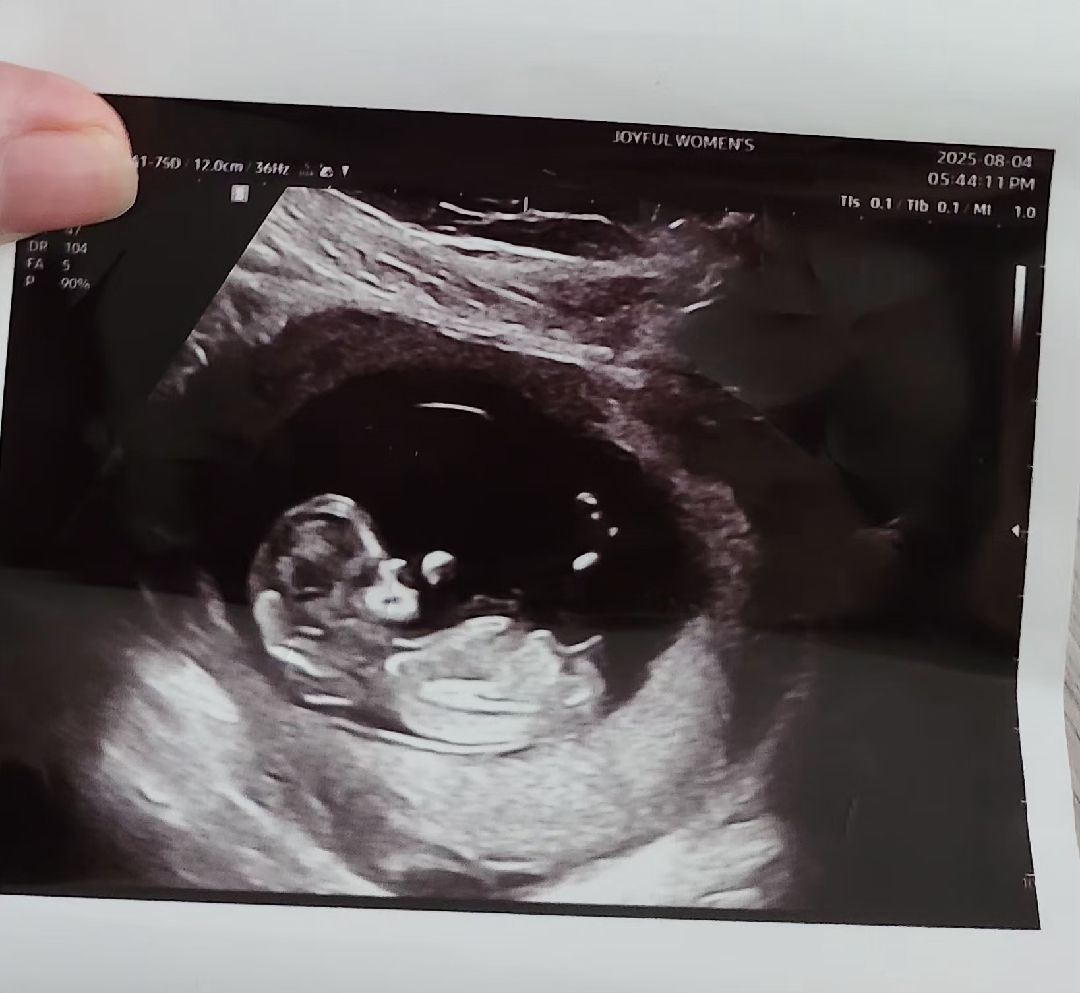

11주 6일찬데 각도법 알 수 있나요?